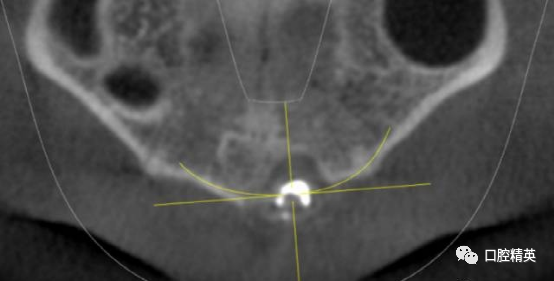

CBCT检查发现21内吸收,已做根充。根尖周可见约10mm*7mm*7mm范围低密度影像,近11,22根尖区。边界清楚。可见超充药物,查看病历曾使用碘仿和VITAPEX。

考虑21慢性根尖囊肿。拟定行囊肿切除+根尖切除倒充术。详细交代可能出现并发症,病人理解同意手术治疗。延期进行牙齿美白和美容性修复。完善术前检查,择期手术。